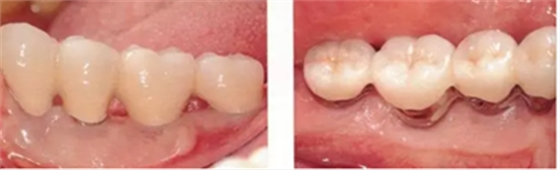

▲圖10-9,10

頰舌側(cè)都獲得了充足的角化齦,菌斑控制狀態(tài)良好。

▲圖10-11,12

佩戴最終修復(fù)體后2年的狀態(tài)。頰舌側(cè)角化齦寬度均充足。